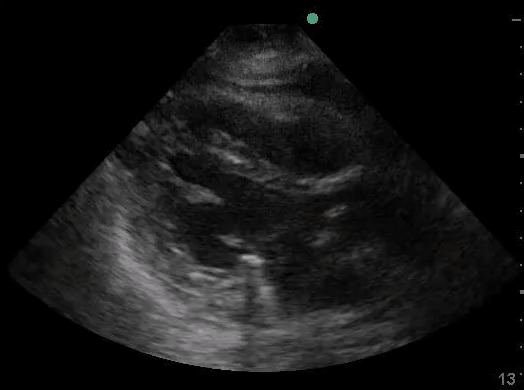

Definitions of cardiac activity and standstill vary across the literature. [14] Most definitions describe ventricular contractility and a decrease in left ventricular chamber size, though discrepancies exist with the identification of atrial or valve flutter. Ultrasound operators may also mistake movement of the chest structures with mechanical ventilation as cardiac activity. Furthermore, weak myocardial contraction, profound bradycardia, or fine ventricular fibrillation can also be confused as cardiac standstill. Examples of cardiac standstill and a weak, bradycardic rhythm are highlighted in Figure 2.

Figure 2. A) Parasternal long view with cardiac standstill. B) Subxiphoid view highlighting weak cardiac activity.

The authors would like to acknowledge Sara Damewood, MD for her review and for providing the cardiac standstill image seen in Figure 2. The authors also thank John Collins for assisting with the creation and editing of Figure 1. Last, the authors would like to thank Jessica Schmidt, MD, MPH and Dana Resop, MD, for their thoughtful review and feedback.